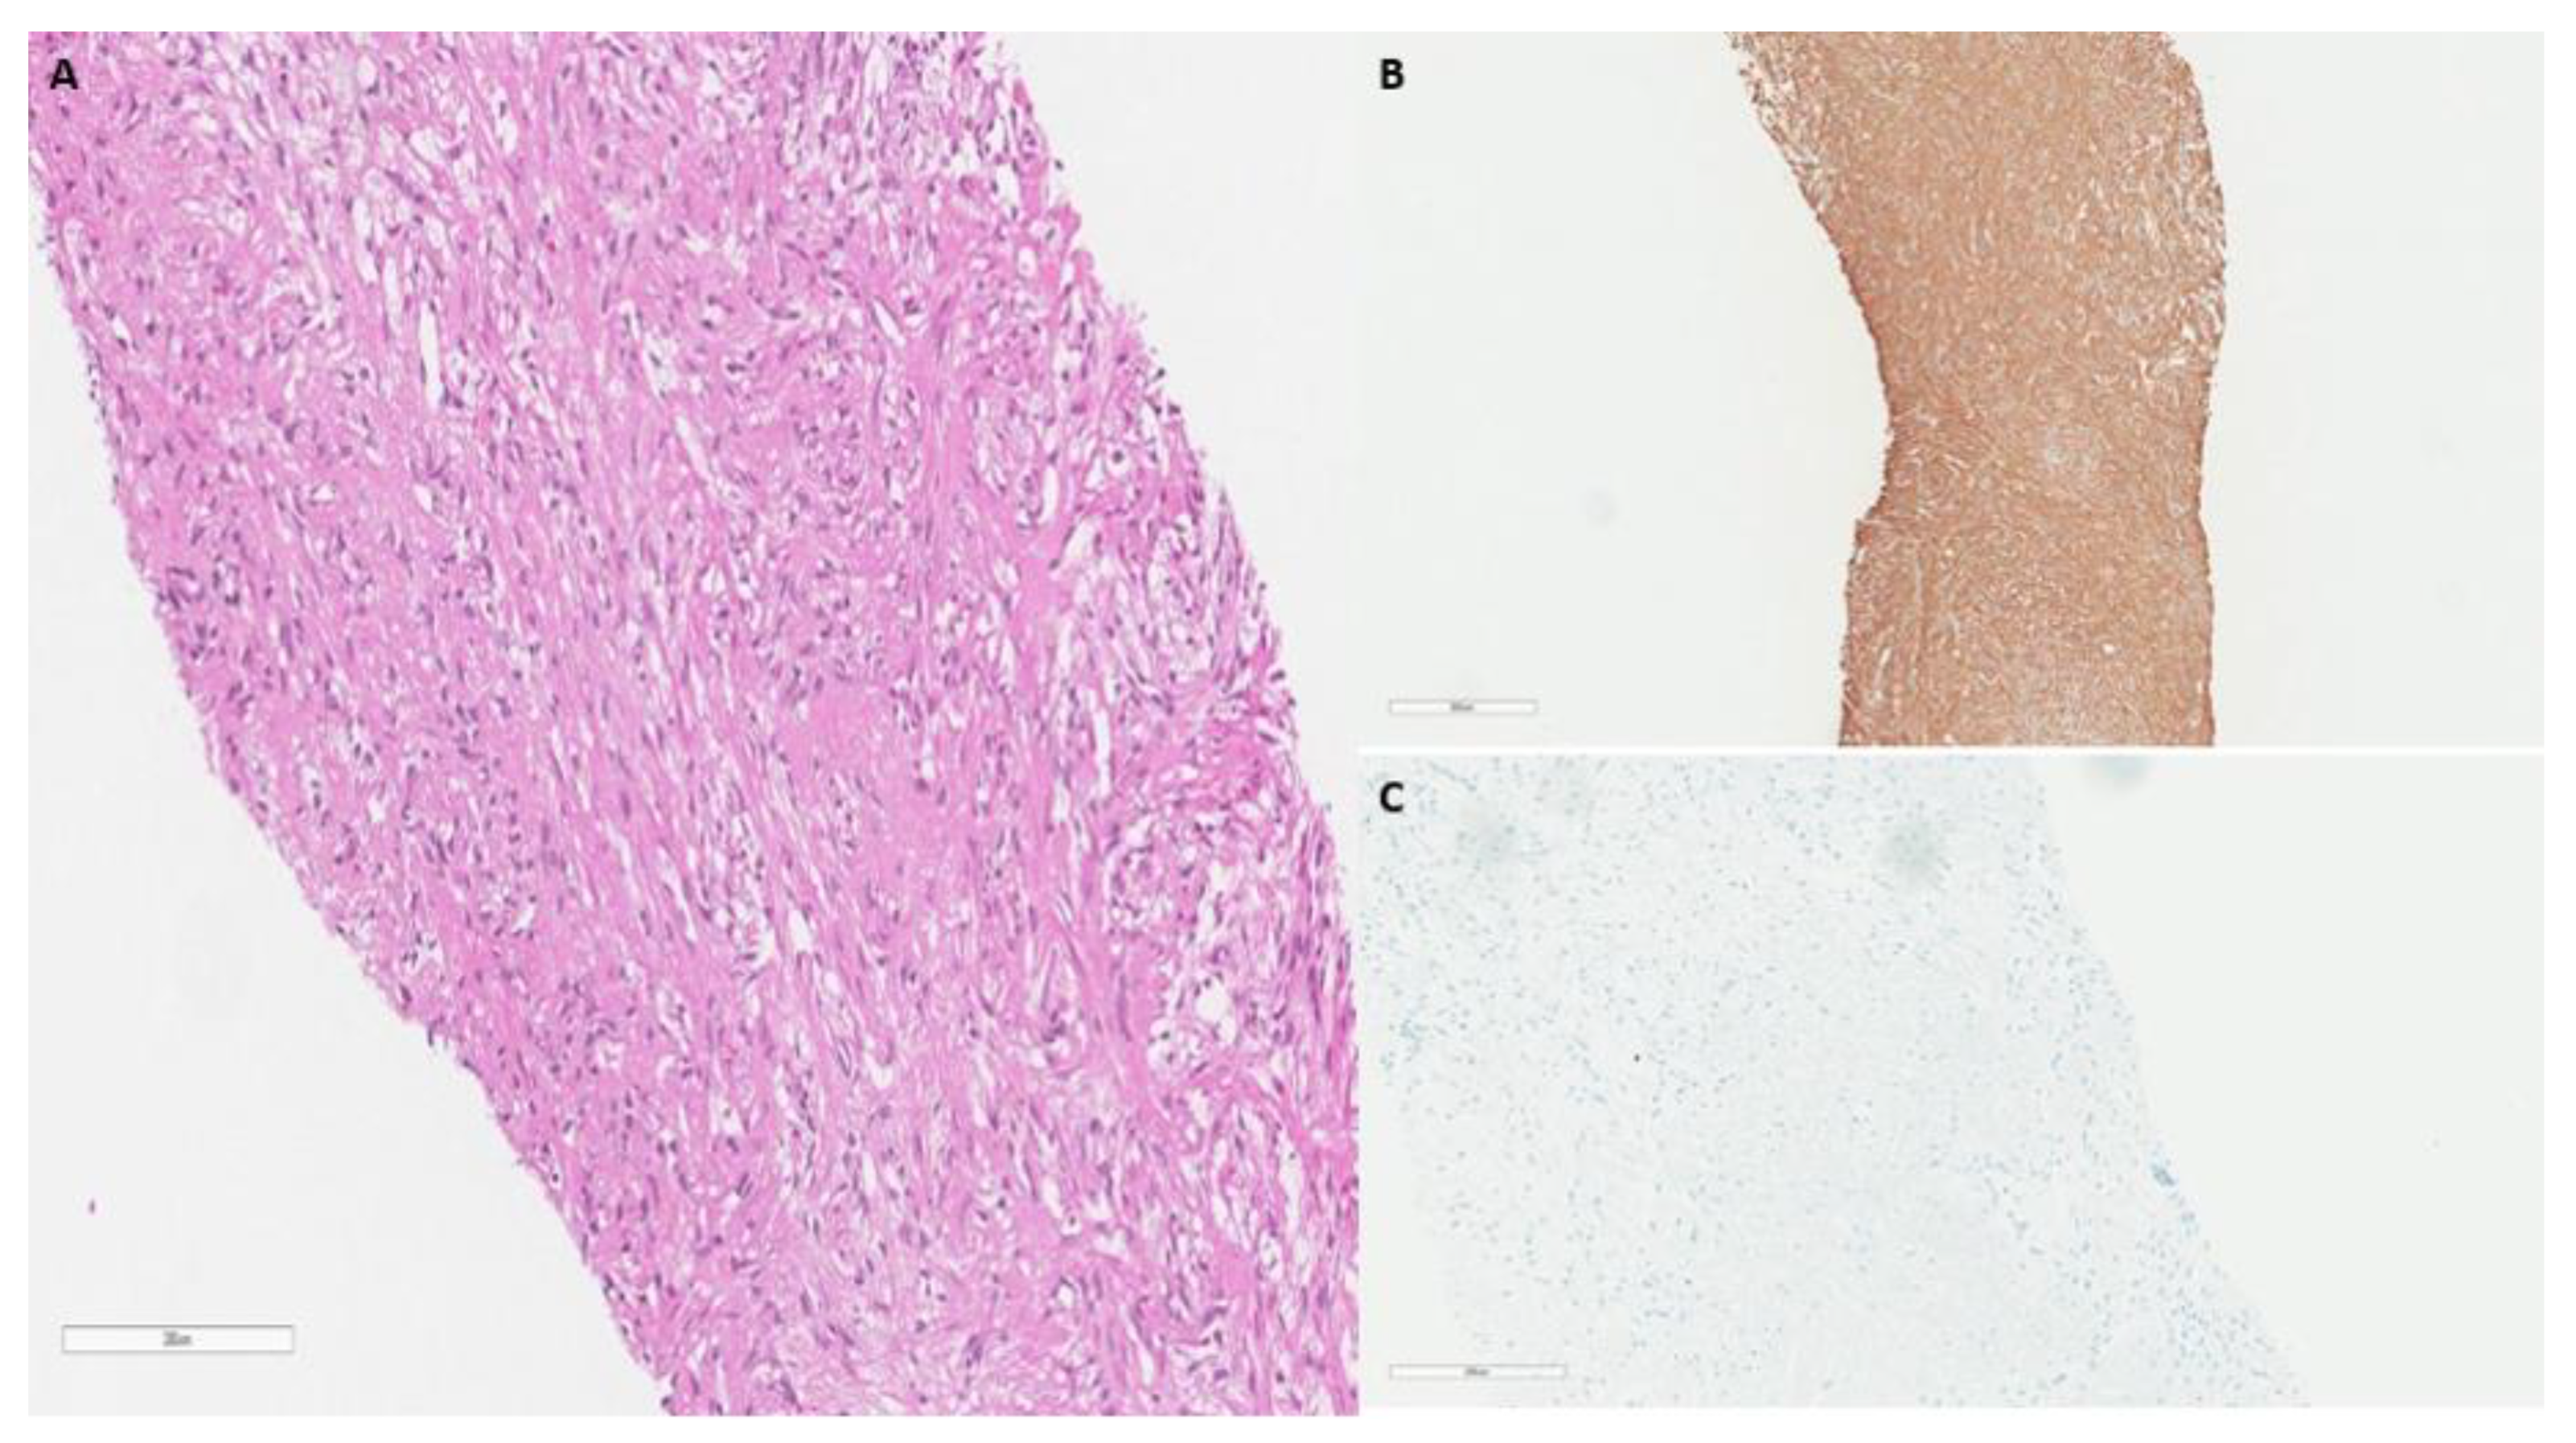

2. Case Report